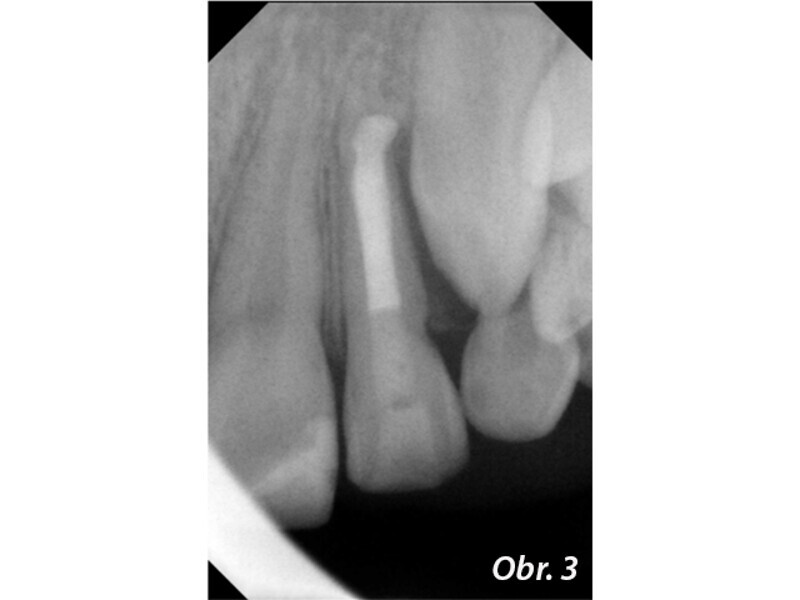

Endodontické ošetření zubů s nedokončeným vývojem kořene